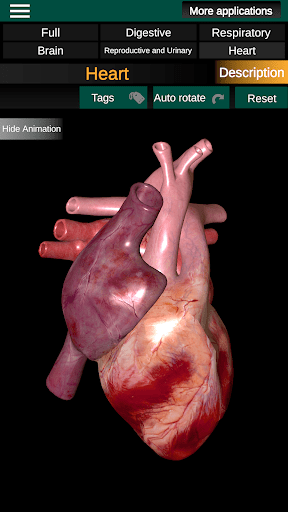

* Jantung, yang meliputi atrium, ventrikel, aorta, dan animasi organ ini.